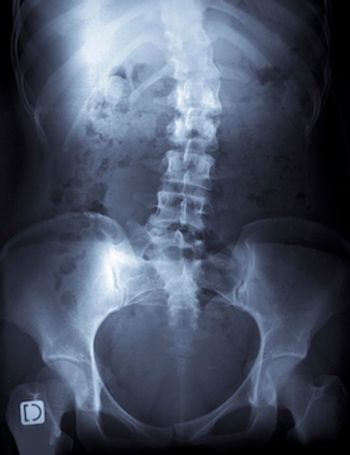

Persistent use of osteoporosis medications was associated with reduced risk of fracture and significantly lower total healthcare costs, a recent analysis of Medicare claims data found.

Bone mineral density (BMD) declines early in the course of type 1 diabetes in men but is little affected by the condition in women, according to a 10-year prospective study.

The largest genomewide association studies ever completed for osteoporosis identified 899 loci, or regions, in the human genome associated with low bone mineral density, 613 of which have not yet been discovered. The Stanford University School of Medicine researcher who made the finding said that widespread genetic screenings could predict a person's future risk of osteoporosis and bone fracture.